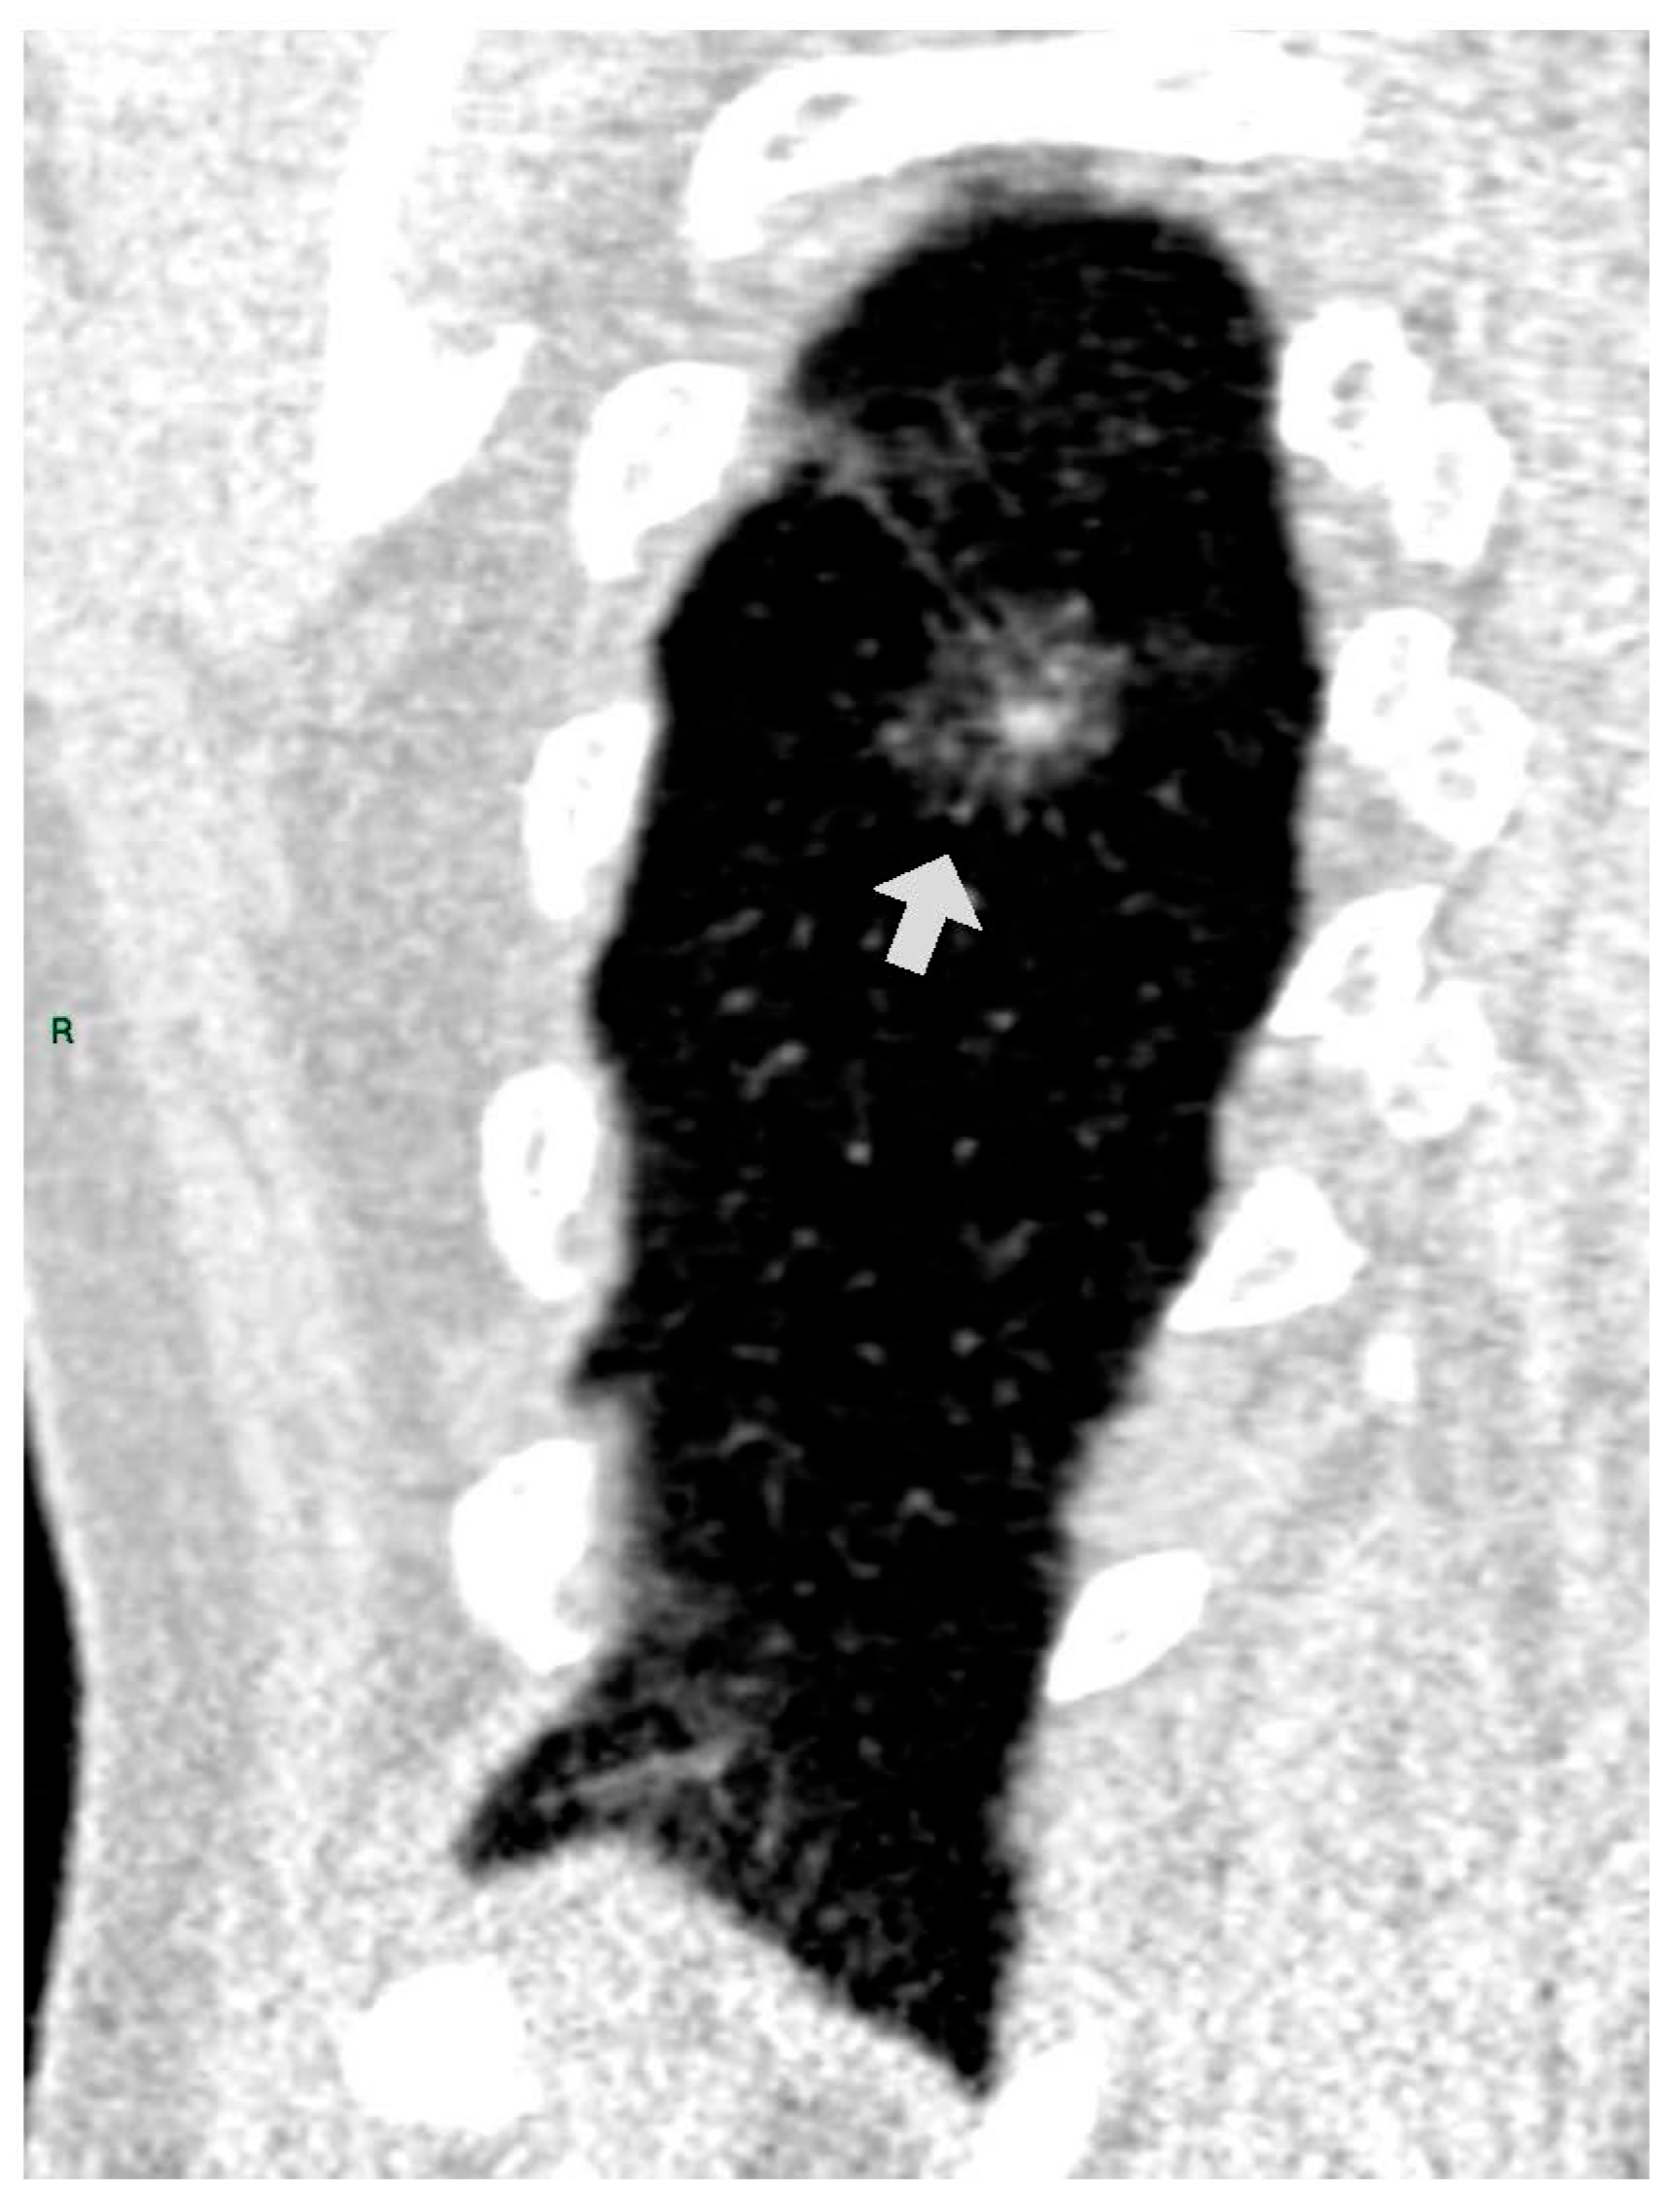

CT images were analyzed for the presence of SSNs and their features (number, size, distribution by lobes, number of involved lobes, and solid components). SSNs were classified into pure ground glass, heterogenous ground glass, and part-solid nodules based on their attenuation on CT images and measurable soft tissue components [5] (Figure 1, Figure 2 and Figure 3).

Figure 3. PSN in RLL (coronal reformation plane).